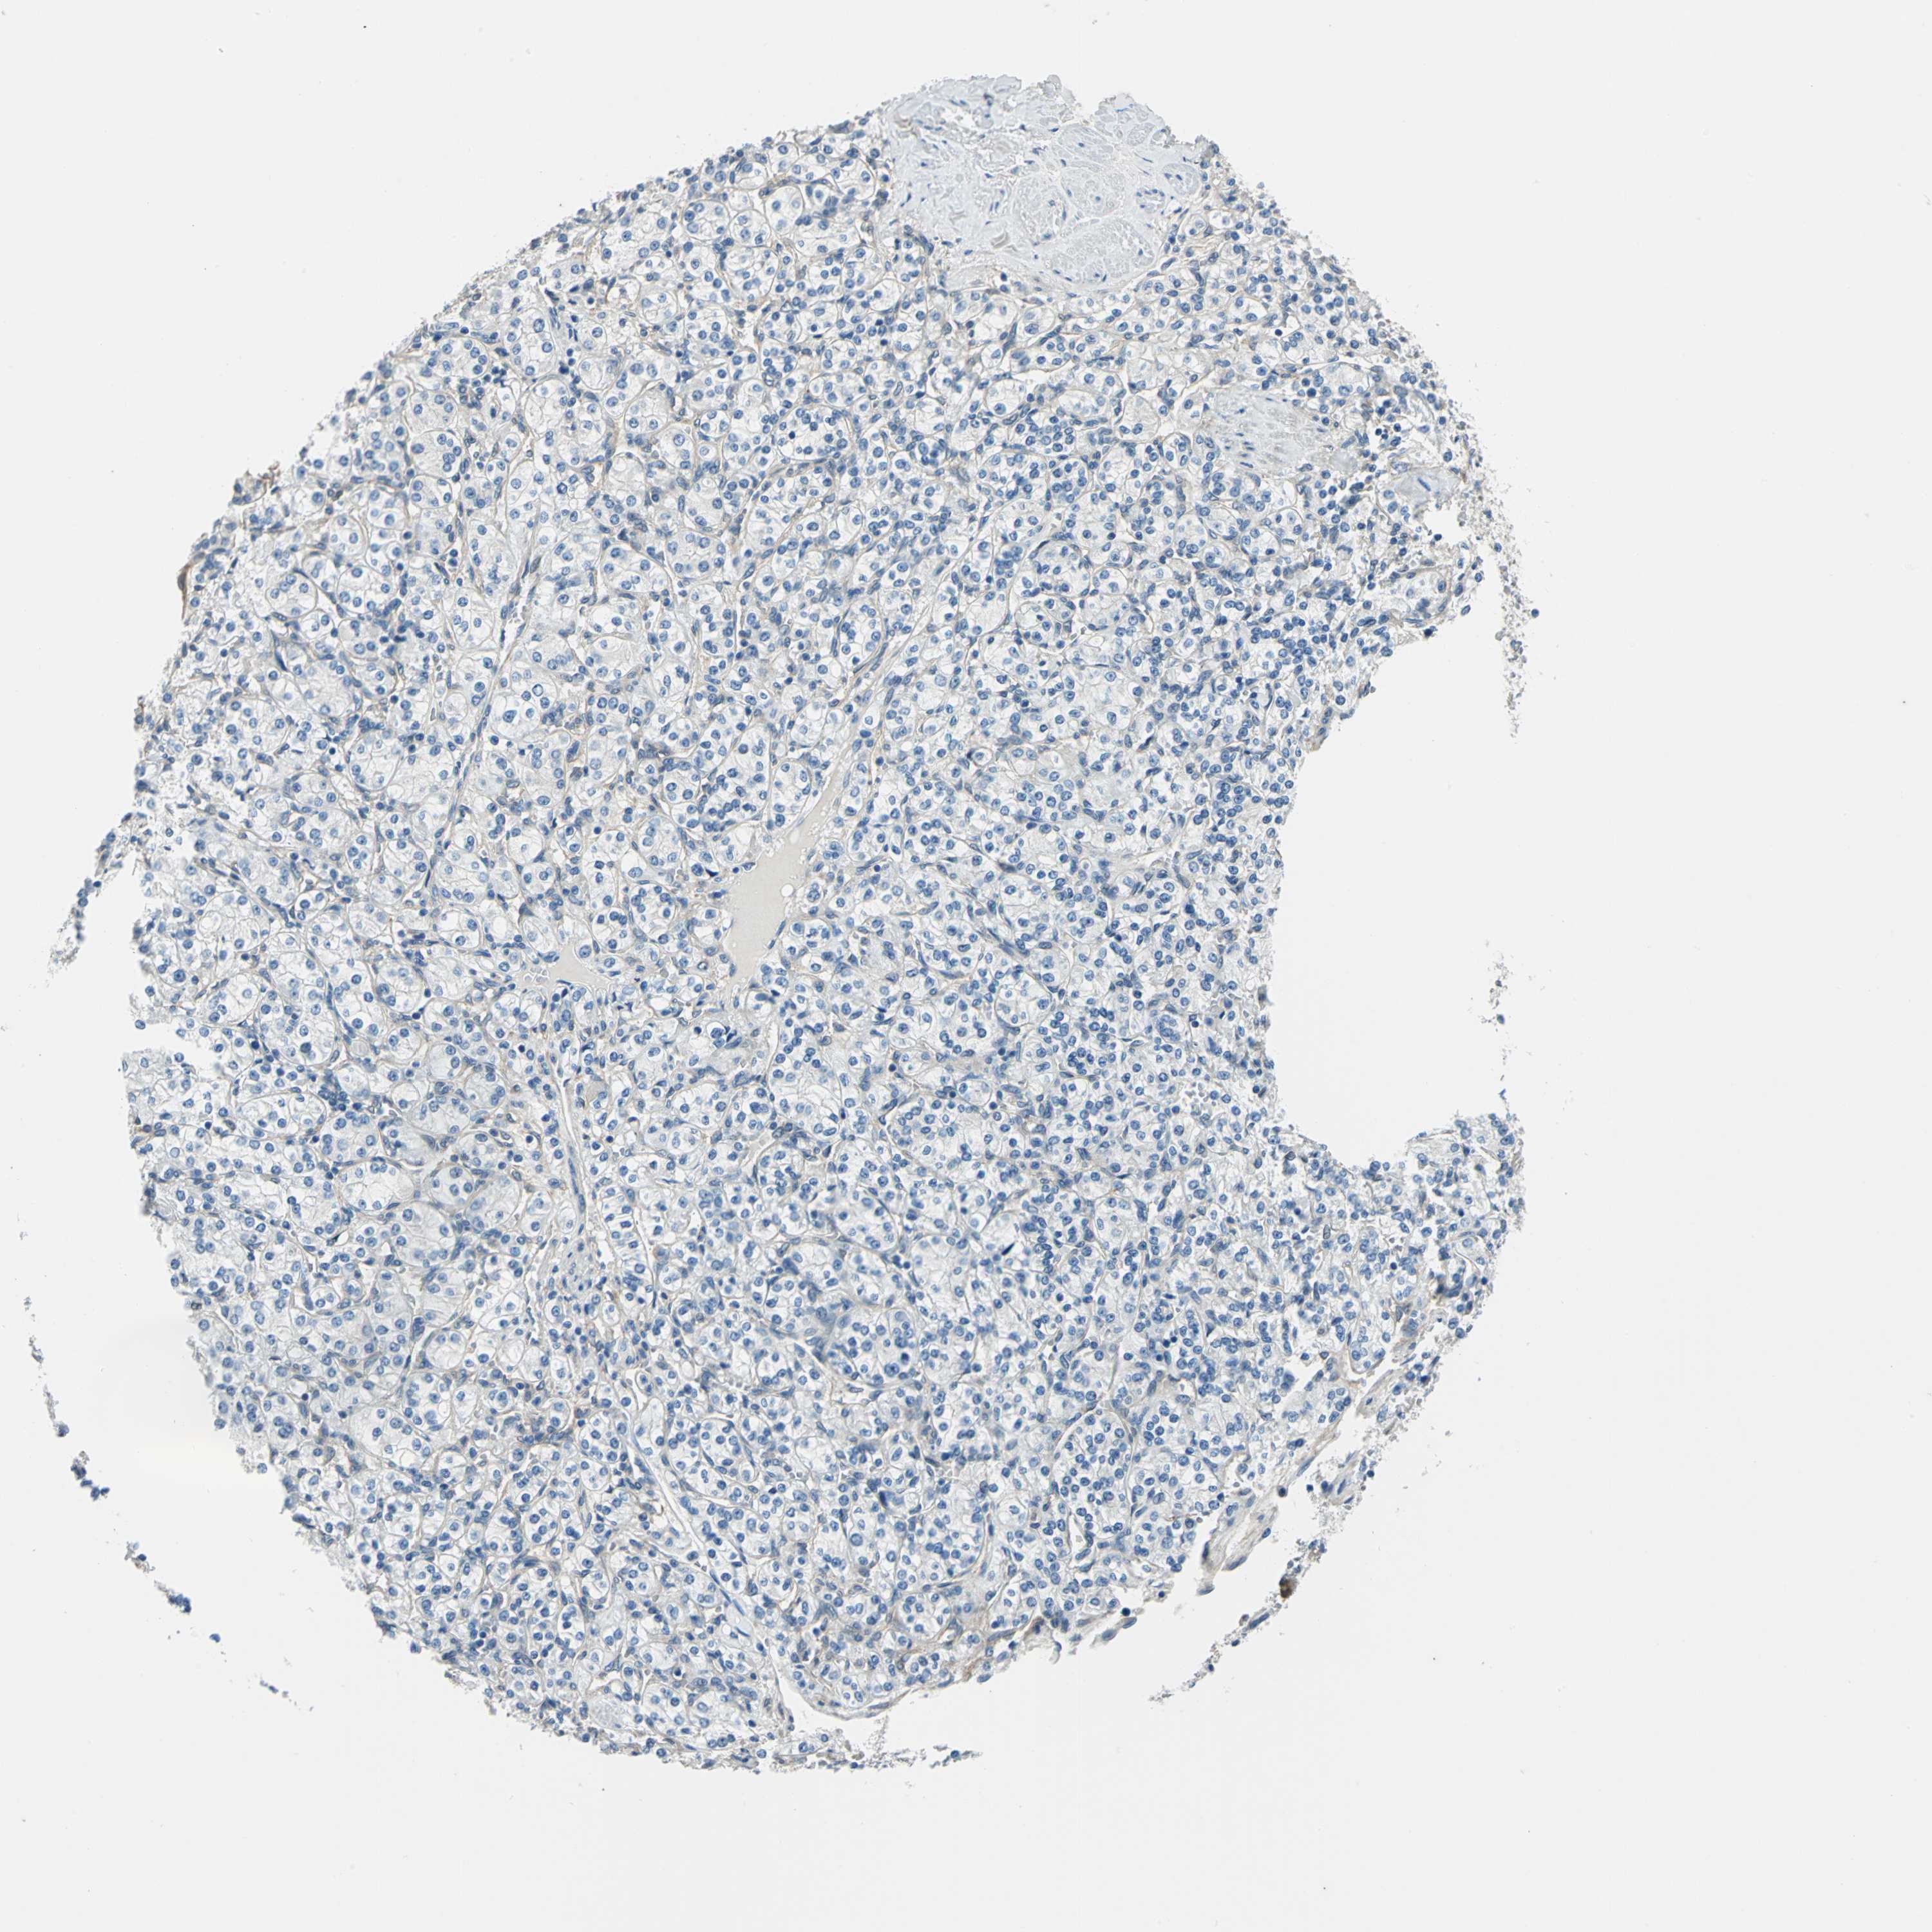

Renal cancer

Kidney chromophobe